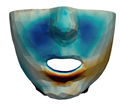

2.5.2. Soft Tissue

- Segmentation of the maxilla and mandible. For all patients, the highest error (except for the neck, which is not clinically relevant as discussed above) appears near the cut areas, both of the maxilla (e.g., patients M5 and M7) and the mandible (e.g., patients M1 and M3). This is probably due to the presence of fixation plates and/or bone grafts in the real result (e.g., patient M10, whose maxilla was not segmented, but where the presence of bone graft has been confirmed by the surgeon who carried out the intervention). As a consequence, patients with a segmented maxilla and/or mandible show in general larger error than those without segmented bones. However, the smooth coupling method proposed in Section 2.3.3 reduces considerably the error in cut areas, as shown in Figure 2.